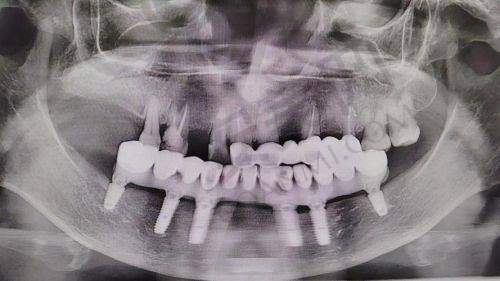

all - on - 4 半口种植牙是一种精良的牙齿种植技术。它通过在牙槽骨内植入四颗种植体,然后利用这四颗种植体来支撑半口牙桥,从而实现半口牙齿的修复。与传统的种植牙技术相比,all - on - 4 半口种植牙具有许多优势。

首先,手术时间短。传统的半口种植牙可能需要植入更多的种植体,手术过程复杂,时间较长。而 all - on - 4 半口种植牙只需要植入四颗种植体,大大缩短了手术时间,减少了患者的痛苦。其次,费用相对较低。由于减少了种植体的使用数量,all - on - 4 半口种植牙的费用相对传统种植牙更为亲民。末尾,稳定性好。四颗种植体呈特定的角度植入牙槽骨内,能够提供足够的支撑力,使牙桥更加稳定,咀嚼功能也能得到良好的修复。

尤其是对于牙槽骨条件不太好的患者,all - on - 4 半口种植牙也具有一定的优势。因为该技术可以通过特殊的种植角度,在相对较少的牙槽骨上实现稳定的种植。不过,患者的身体状况也需要符合一定的要求。例如,患者不能患有重度的心血管疾病、糖尿病等全身性疾病,否则可能会增加手术风险。